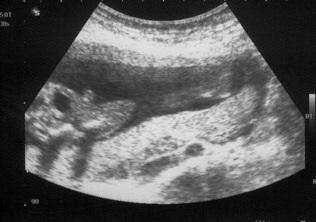

Es war unglaublich. Si ein Kerlchen. Wisst ihr wie es gelegen hat als wir anfingen mit dem Ultraschall: Beide Hände übern Kopf, ein Bein angewinkelt und darauf der Fuß vom anderen Bein. Als wenn da drin Holiday am Strand angesagt ist. Einfach klasse Beim Geschlecht hat sie ein paar mal geschaut ob es nicht doch die Nabelschnur ist, aber sie meinte es sieht nach einem Jungen aus. Zu Feindiagnostik darf ich in etwa 3 Wochen. Dort lassen wir den Beweis noch mal bestätigen. Schaut mal links im Bild:

Bild zu VU mit Outing und Beweisbild *freu* - Forum für Juli - Mamis